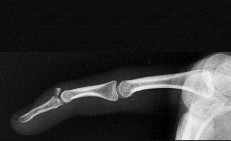

- الأشعة السينية (X-rays): هي الخطوة الأولى في تقييم الكسور، الخلوع، وتغيرات التهاب المفاصل. تساعد في تحديد مدى تدهور العظام والمسافات المفصلية. على سبيل المثال، تُظهر صور الأشعة السينية كسور السلاميات

أو كسور قاعدة العظم المشطي الخامس